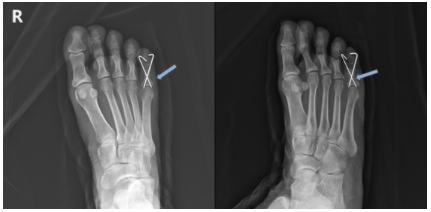

발가락 골절 후, 의료 서비스 제공자와 상담이 필수입니다. 의사는 X-레이 및 기타 진단 검사를 통해 골절 정도를 평가하고 적절한 치료 방법을 제시할 것입니다. 부상된 발가락은 부목, 깁스 또는 테이핑을 통해 안정화될 수 있습니다.